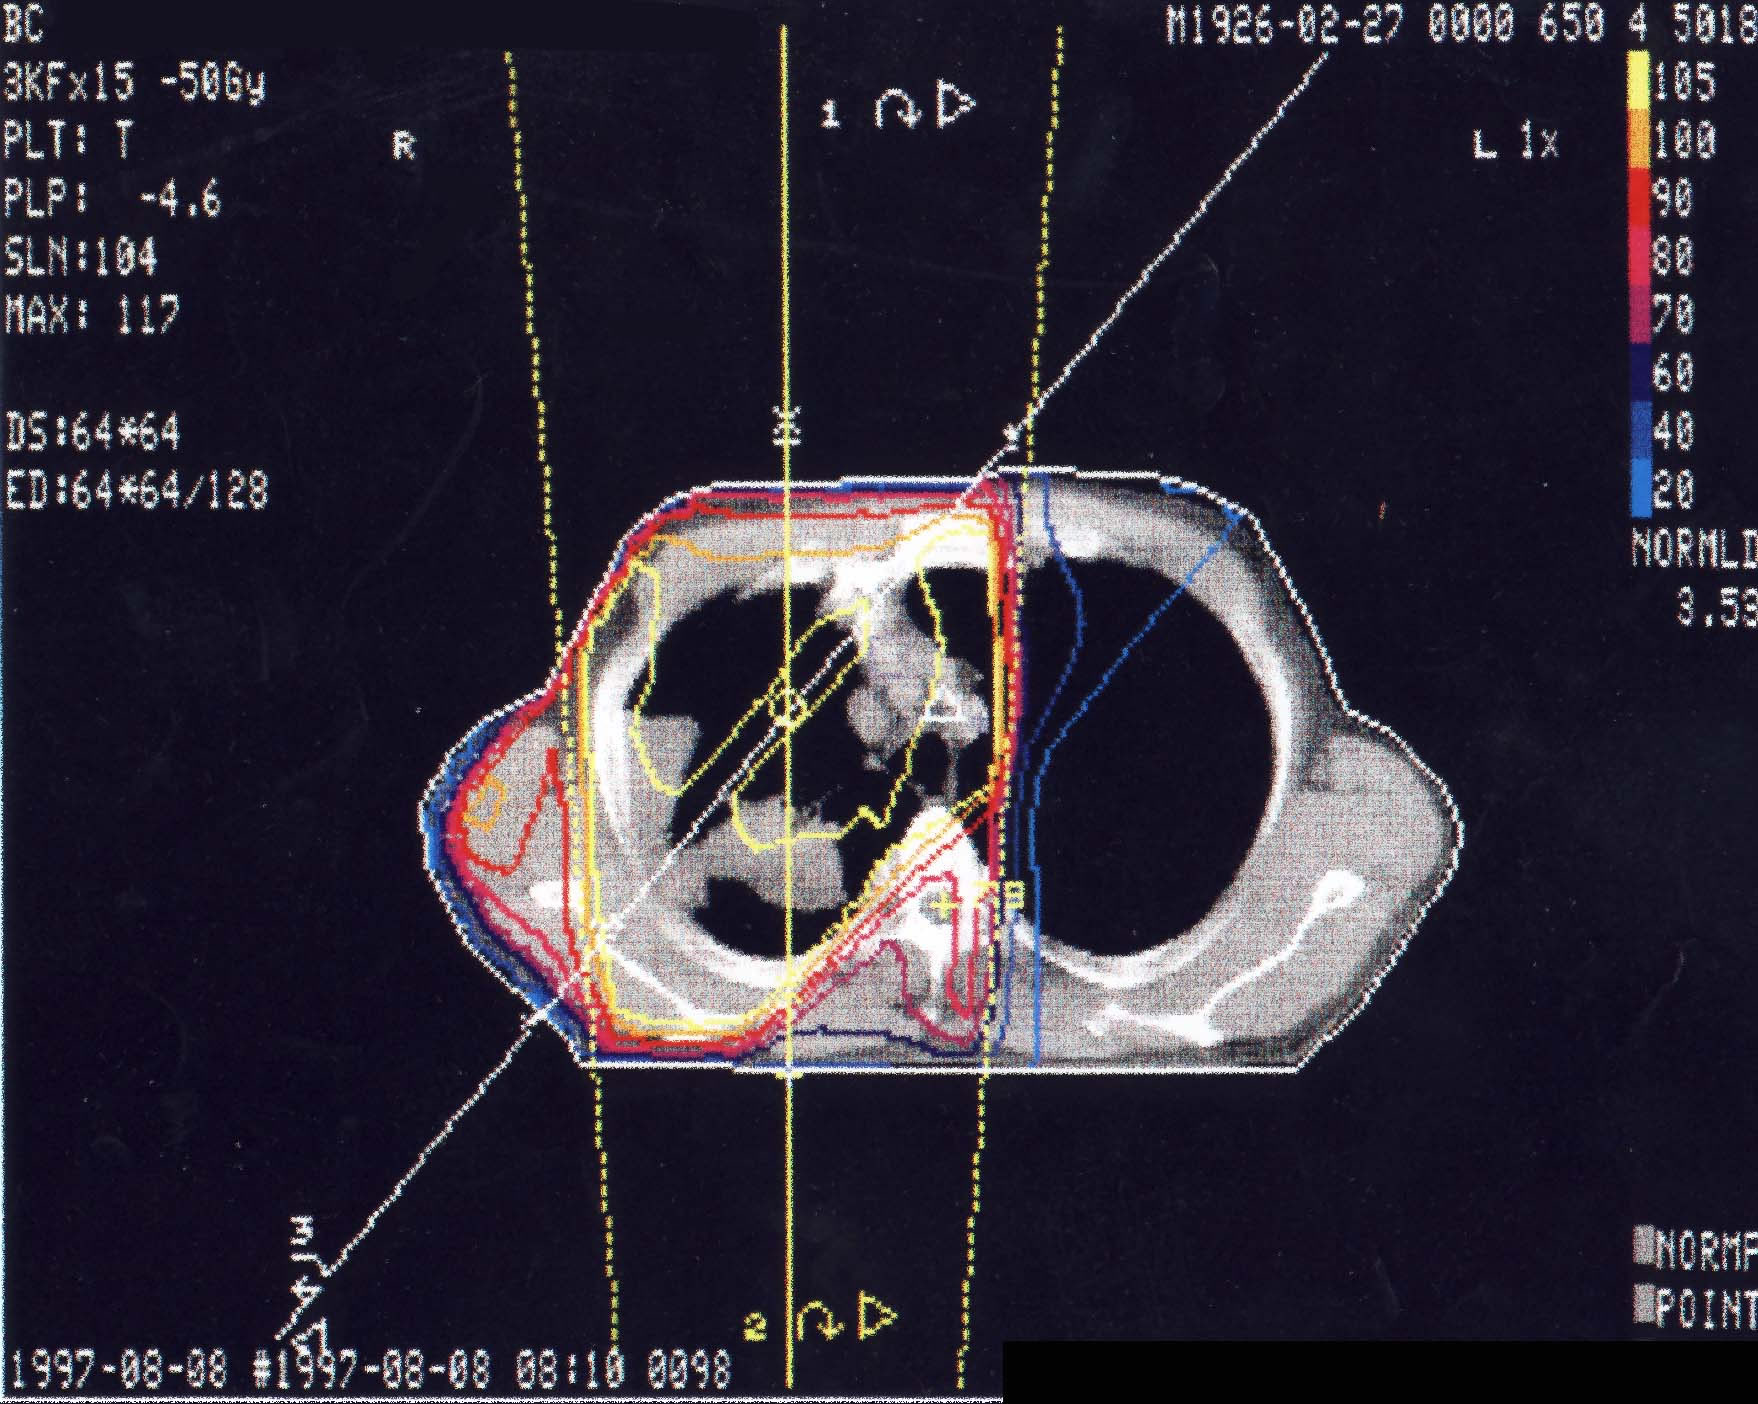

Bronchialkarzinom: Bestrahlungsplan